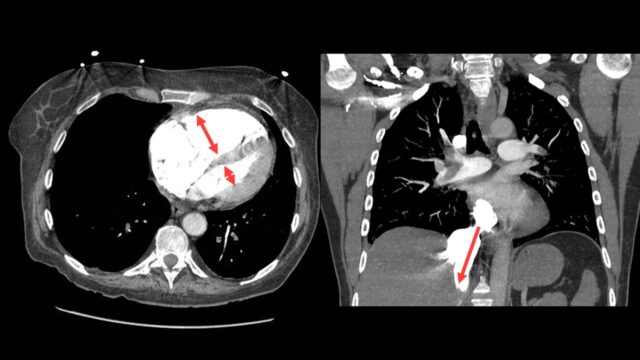

There are two things that I do look for on the CT scan to predict severity the size of the RV compared to the left with the position of IVS

and i look for contrast reflux into the IVC. An RV under acute pressure will fail. When the RV fails it blows out and it fails to pump effectively with > contrast backing up in the IVC. If your radiologists are not reporting this routinely they should be.

The other thing I look for on CT is chronicity. There are lots of patients out there with dilated poorly functioning right ventricles from other causes, mostly chronic lung disease. Some of these patients will also have PEs. Can you distinguish chronic from acute changes?

Lets use an example. This a 50M transferred to you from outside hospital with intermediate-high risk PE. You can see the PE here. It’s segmental, it is definitely not big. The RV is massive there is contrast reflux. These are all signs that I’ve been telling you suggest that bad things are happening.

However…

Look further and you can see the main PA is much bigger than the aorta, that takes time to develop. When you look with echo you can see a massive RV but it’s big and chunky and looks like its been lifting kettle bells for years. The bottom is a little doppler way of measuring right sided heart pressures and it suggested that the right heart pressures were far too high for this to be an acute event. This case is actually someone with primary pulmonary hypertension that just happened to have a PE.